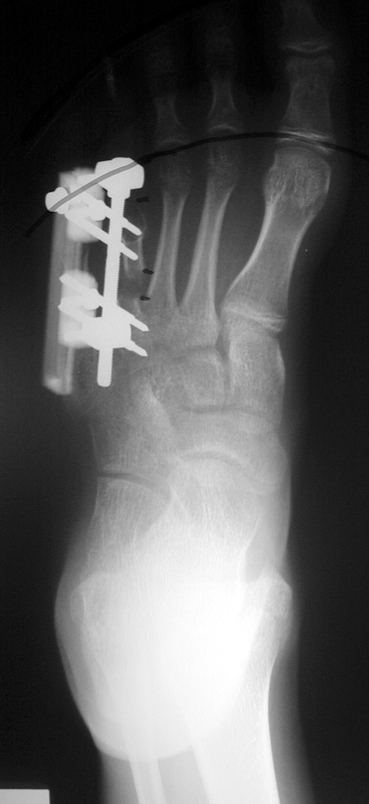

Doğuştan metakarp ve metatars kısalıklarının redavisi için pek çok teknik tanımlanmakla birlikte en çok akut uzatma sonrası kemik uçlarına greft konması ve distraksiyon osteogenezi (kallotasis) kullanılmaktadır. 1 cm.den daha fazla uzatma gereken olgularda kallotasis yöntemi önerilmektedir. Kliniğimizde de metatars ve metakarp uzatma için unilateral eksternal fiksatör ve sirküler eksternal fiksatör yardımıyla distraksiyon osteogenezi yöntemi tercih edilmektedir.